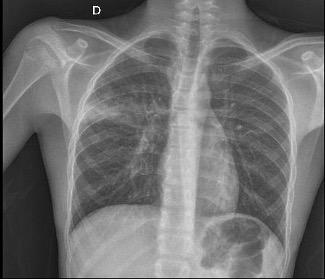

Un ragazzo di 15 anni giungeva presso il nostro pronto soccorso per ipoalimentazione dovuta a mucosite insorta da due giorni, progressivamente ingravescente. Per la presenza di febbre e tosse nei cinque giorni precedenti l’accesso in ospedale era stata prescritta dal curante terapia con amoxicillina/clavulanato e prednisone assunta per tre giorni. Un paio di giorni dopo l’insorgenza della febbre veniva segnalata la comparsa di lacrimazione oculare bilaterale e bruciore minzionale. All’EO all’ingresso il ragazzo presentava parametri vitali stabili, presenza di lacrimazione binoculare purulenta associata a congiuntivite emorragica [Figura 1], xerosi labiale e lesioni simil-aftose diffuse a labbra, cavo orale e orofaringe, minima adenopatia laterocervicale bilaterale. All’auscultazione si apprezzava murmure vescicolare diffuso ubiquitariamente in assenza di rumori patologici aggiunti; restante obiettività nella norma, eccetto un ritardo di crescita puberale (noto, per cui era già stata avviata presa in carico auxo-endocrinologica). All’anamnesi patologica remota veniva segnalata adenotonsillectomia all’età di 5 anni, mentre l’anamnesi familiare risultava muta. Agli esami ematochimici effettuati al momento dell’accesso non risultavano alterazioni significative, a eccezione di una neutrofilia relativa; l’emogasanalisi e l’esame chimico-fisico urinario risultavano nella norma [Tabella 1], il tampone SARS-CoV-2 e la ricerca dei virus respiratori su tampone nasofaringeo erano risultati negativi. Durante il ricovero ospedaliero venivano avviate idratazione endovenosa, terapia antidolorifica e antivirale nel sospetto di mucosite erpetica (sospesa dopo esclusione di infezione in atto; sierologia per HSV 1/2 negativa, così come per EBV, CMV e Coxsackie B). Il secondo giorno di ricovero il ragazzo presentava comparsa di lesioni piane, iperemiche, rotondeggianti con componente vescicolare al centro, non pruriginose, sparse al dorso, al collo e alla gamba [Figura 2], ulcerazione del glande con coinvolgimento del meato uretrale esterno e peggioramento della disuria, progressione della mucosite, aggravata da lesioni crostose e fissurazioni labiali [Figura 3] con rifiuto dell’alimentazione. È stata avviata presa in carico multidisciplinare (oftalmologica, odontostomatologica, dietistica e anche psicologica per escludere eventuale componente depressiva associata, slegata dalla condizione acuta oggetto della nostra valutazione). È stata quindi applicata neomicina a livello genitale, terapia topica oculare a base antistaminica e antibiotica, detersione del cavo orale con soluzione a base di clorexidina e gel contenente acido ialuronico a scopo analgesico ed è stato avviato fluconazolo endovena a scopo profilattico per evitare candidiasi orale o esofagea. Per la persistenza di tosse e di alcuni episodi di desaturazione fugace veniva eseguita radiografia del torace con ri-

scontro di addensamento polmonare destro. Alla luce di questo reperto, nel sospetto di una polmonite da germi atipici, è stata avviata, in accordo con gli infettivologi, terapia con claritromicina endovenosa ed eseguito film array dell’escreato, risultato successivamente positivo per Mycoplasma pneumoniae

destro e aree sopra-scissurali.

Figura 4. Radiografia del torace con evidenza di ispessimento periscissurale